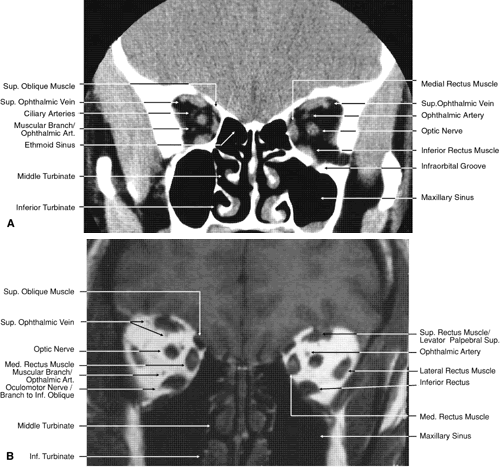

The globe is shown in Figure 12. The orbit and periorbital structures are shown in Figures 13 through 16, and the optic canal is shown in Figures 17 through 26. The cavernous sinus and optic chiasm are shown in Figures 27 and 28, and the posterior visual pathway and cranial nerves are shown in Figures 29 through 33.

Fig. 17. Coronal images through anterior orbit. A. Computed tomography scan. B. T1-weighted magnetic resonance imaging.

Fig. 18. Coronal images through midglobe. A. Computed tomography scan. B. T1-weighted magnetic resonance imaging.

Fig. 19. Coronal images through midorbit posterior to the globe. A. Computed tomography scan.B. T1-weighted magnetic resonance imaging.

Fig. 20. Coronal images through orbital apex. A. Computed tomography scan. B. T1-weighted magnetic resonance imaging. C. Anatomic section of a cadaver head at the level of the orbital apex.